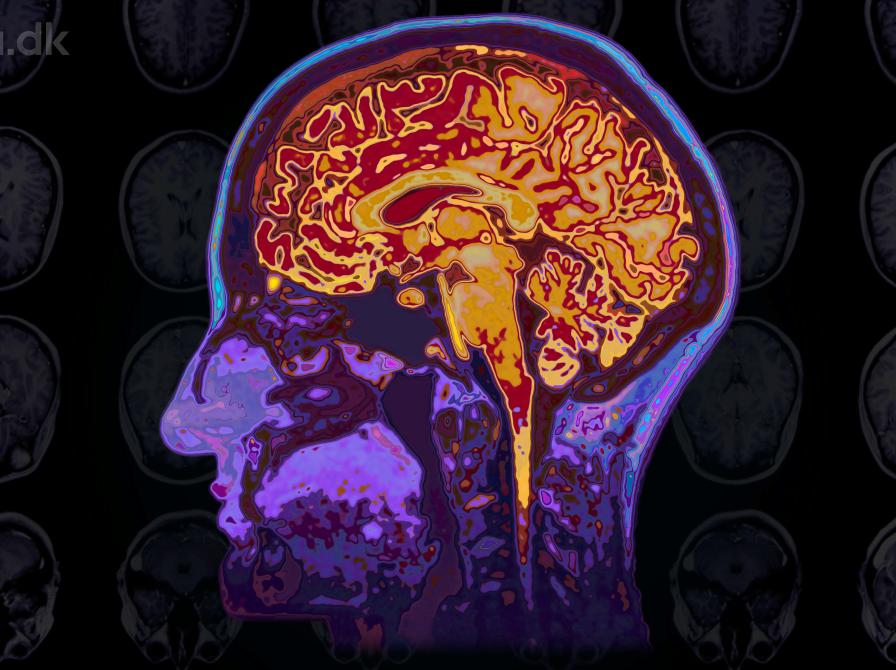

Ved Morten Kringelbach, professor i neuroscience ved Institut for Klinisk Medicin, Aarhus Universitet og ved The Queen's College, University of Oxford.

Hvordan reagerer vores hjerner på fx natur, mad og musik? Hjerneskanninger og computermodellering bidrager til nye indsigter i hvordan nydelse, begær og meningsfylde er indrettet i hjernen og, med dem, hvordan vores livskvalitet kan forbedres.